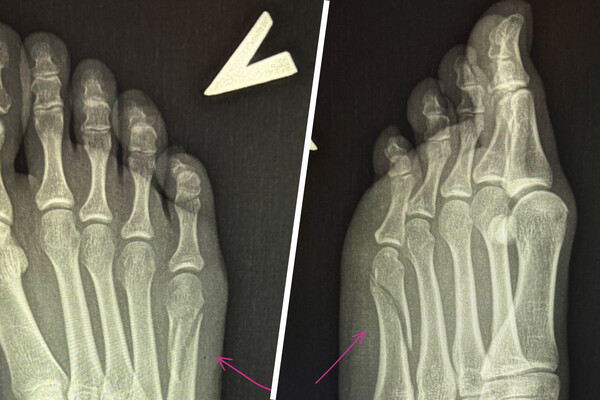

Вавилова опубликовала сообщение в ночь на 28 сентября 2025 года, приложив к нему рентгеновские снимки, на которых видна трещина в кости, ведущей к мизинцу. Она отметила, что из-за травмы не может заниматься привычными делами и вынуждена оставаться дома для отдыха.